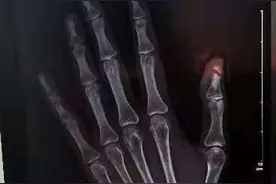

长沙晚报掌上长沙4月10日讯(全媒体记者 杨云龙 通讯员 陈韬)“穿针引线,缝缝补补”是一项基本的生活技能,如今已经应用于临床,尤其是骨科、显微外科的医生们经常用到。记者今日从长沙市第四医院获悉,该院骨科二病区成功为一名右手大拇指被车门夹断的患者接上断指。

手指被门夹伤是日常生活中较为常见的外伤,十指连心,疼痛可想而知。前不久,长沙4岁的男孩童童就不慎被家中铁门夹伤,当即食指指尖离断,出血不止。童童嚎啕大哭,惊慌不已的爸爸把断指随手装进口袋后,立即将孩子送至长沙市第三医院。